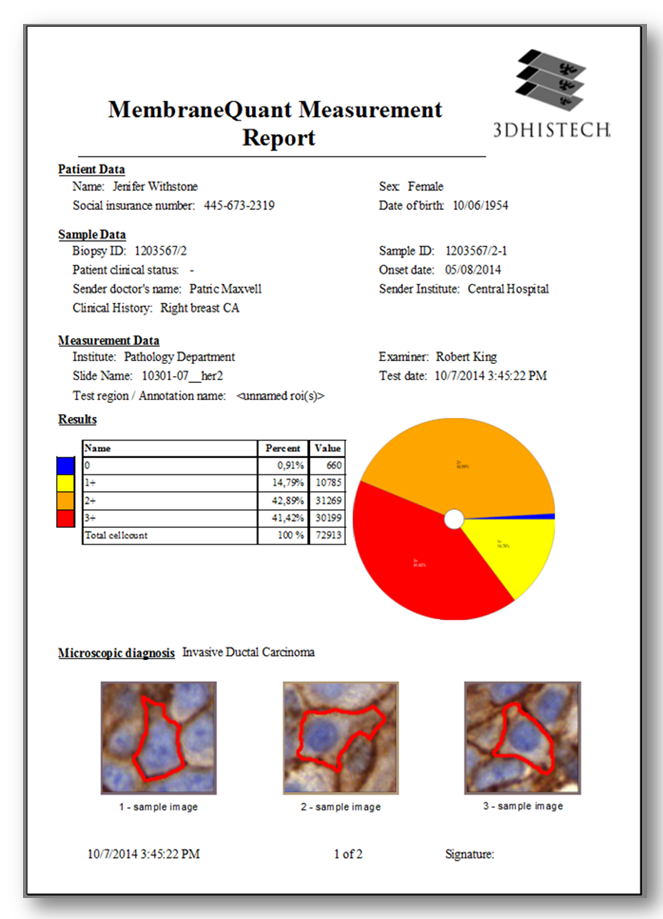

MembraneQuant is a cell membrane detection software application that can be used for the quantification of IHC stained histological samples. This module measures cell morphology and stain density, reports intensity-based core ranges, overall scores and positivity percentages (including H-Score), distinguishing the continuous membrane stain from the moderate stain.

This module has IVD approval for the quantification of Her2 expression in breast tissue samples.